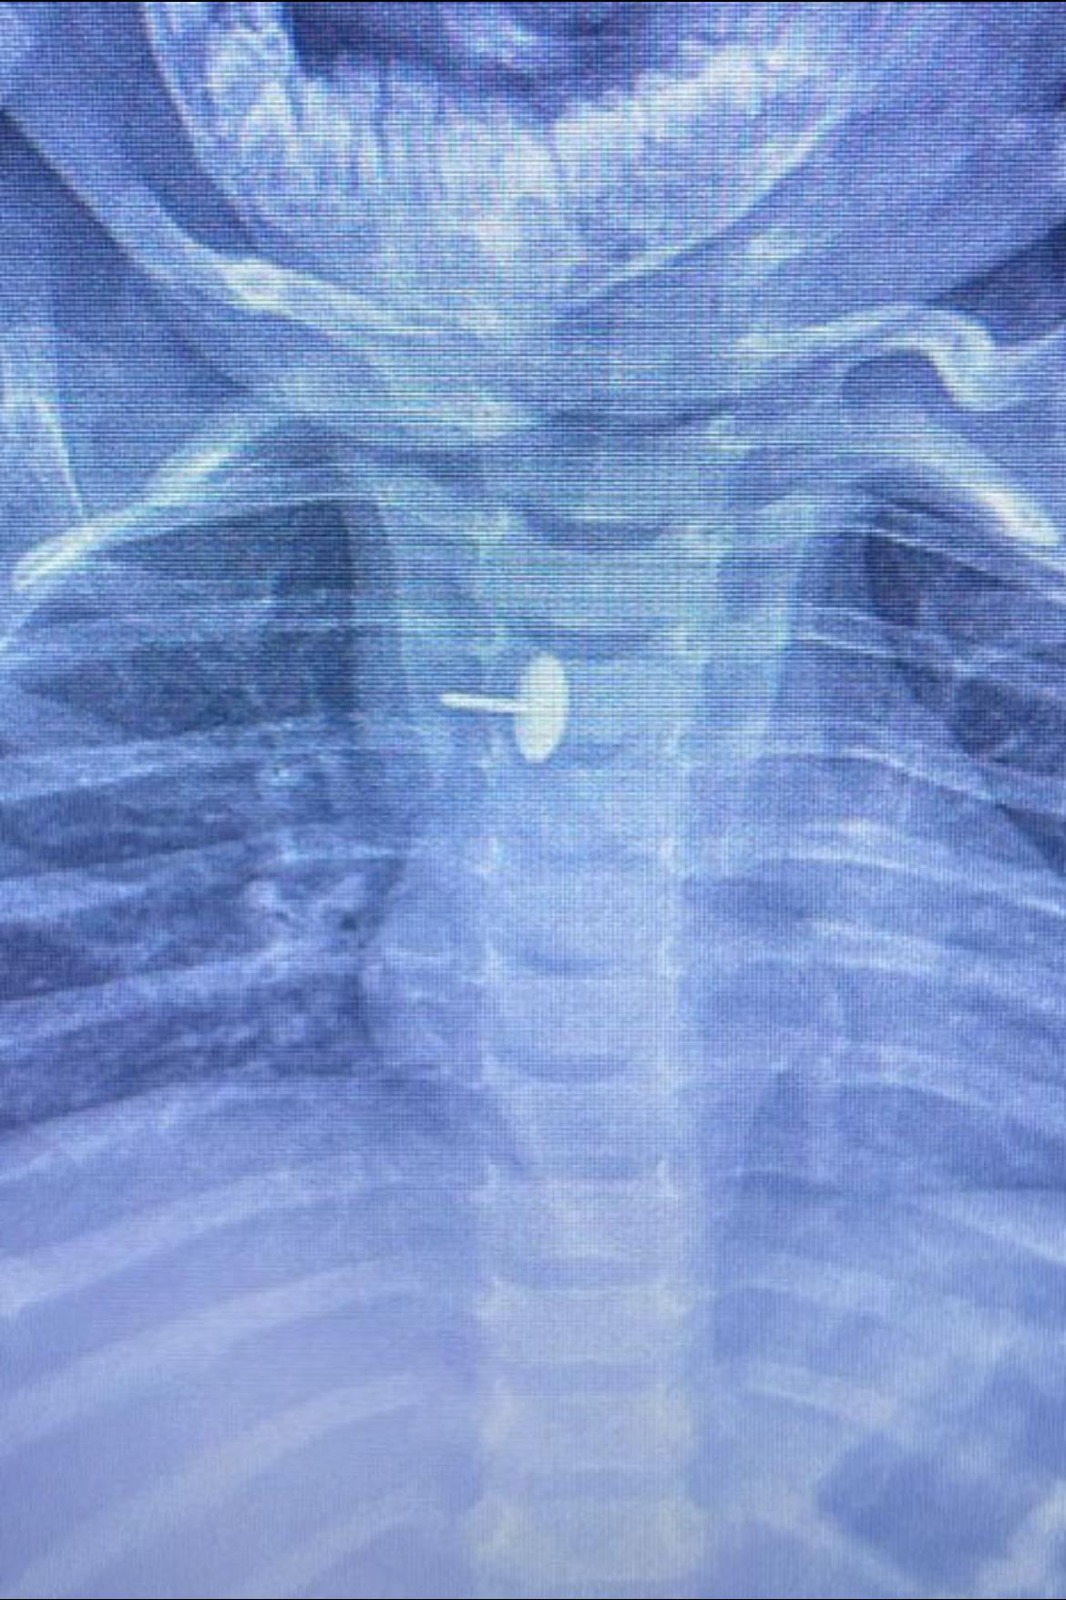

نجح فريق قسم جراحة الأطفال، بمستشفى الأطفال التخصصي ببنها، بمحافظة القليوبية، بقيادة الدكتور محمد متولي رئيس قسم جراحة الأطفال، في إجراء عملية دقيقة لاستخراج دبوس ضغط من مريء طفلة عمرها سنة و7 أشهر، كانت قد ابتلعته منذ 6 أشهر.

الجسم الغريب استقر داخل جدار المرئ

كشفت مستشفى الأطفال التخصصي ببنها، في بيان لها، أن الجسم الغريب استقر داخل جدار المريء، مما تسبب في عدم قدرة الطفلة على البلع طوال هذه الفترة، وجعل حياتها في خطر دائم.

أوضحت المستشفى أن العملية تمت باستخدام منظار الجهاز الهضمي، وجهاز الأشعة "سي- آرم"، ومنظار القصبة الهوائية، وسط أعلى درجات التركيز والدقة، ليكتب الأطباء نهاية سعيدة لقصة مليئة بالتوتر والخطر، وضم الفريق الجراحي كلا من الدكتور وليد محمد، والدكتور عبد الله أحمد أخصائي جراحة الأطفال، والدكتور السيد الوصال نائب جراحة الأطفال.

فريق جراحى بالقليوبية يستخرج دبوس ضغط من مرئ طفلة